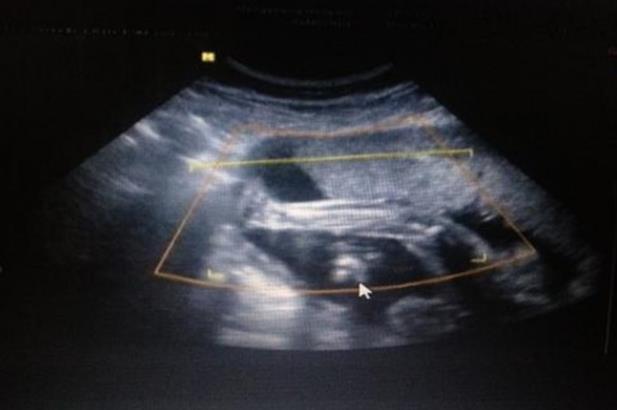

周六一早大姨妈驾到,赶紧预约了周日的试管促排和。今天八点四十到达医院,打印挂号单,然后到四楼六诊室,六诊室换了房间,比以前略挤一些。促排第一天,门口递挂号单和磁卡登记,行程单拿到门外填好,扫夫妻二人行程码截图,然后等着护士叫名字。叫到名字录指纹,交行程单看行程码,然后拿档案夹和磁卡给里面桌子护士。我今天不用抽血,只做B超,第一次去,护士让我上好厕所直接去七诊室等着,刚到七诊室就喊到我。9:35,B超就做完了。慢悠悠下楼吃了个早饭,回来等11:30听医嘱。